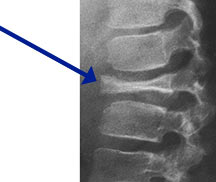

• • The work-up often consists of a physical examination, X-rays, CT scans, MRI, and sometimes bone scans are required.

Radiographic imaging is used to help form a diagnosis. These include X-Ray, MRI, CT and Bone Scans

An example of an Eosinophilic Granuloma MRI is shown.